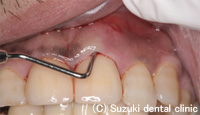

| 歯周ポケットの中を消毒液で消毒 |

フィステルの部分から消毒液が滲んで出でくる |